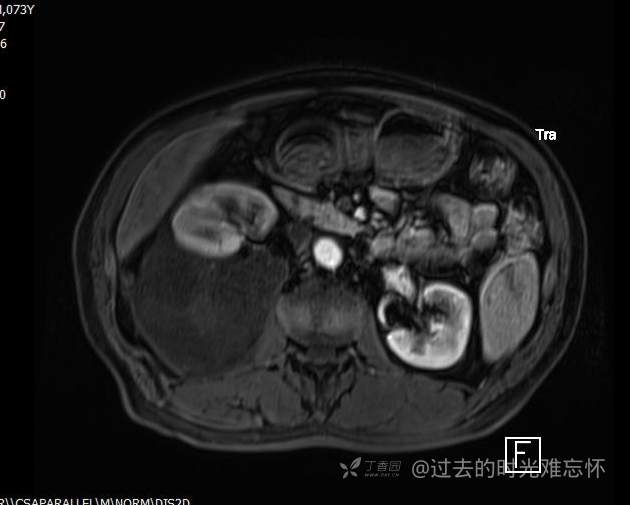

患者性别:男

患者年龄:73岁

主诉:咳嗽1月余。曾有血尿一次。后背部酸痛不适1-2年左右,无明显消瘦。

辅助检查:CT MRI

临床诊断:占位

治疗经过:手术

T1 及 T1压脂